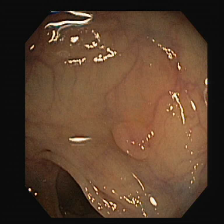

To show the effectiveness of our decoder consistency training approach, we compared our model with and without our consistency training approach. Table 2 shows the results of our model’s performance with and without consistency training. Using our consistency training approach, we are able to reduce false positive rates and improve the segmentation results for Kvasir-SEG [7], ClinicDB [1], ETIS [10], and EndoScene [13] datasets. Sample segmentation results as seen in Figure 2 also support these improvements.

Figure 2: Sample segmentation results of the benchmark models compared with PlutoNet without (Plu nC) and with consistency training (Plu wC). Images shown in the first column belong to Kvasir, ClinicDB, ColonDB, EndoScene, and Etis datasets.